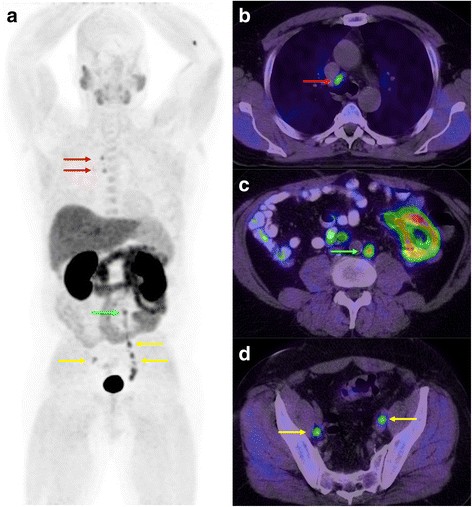

Restaging FCH-PET/CT in a 58 y.o. patient with biochemical relapse following external beam radiotherapy. Gleason sum was 9 on initial biopsy. PSA at time of examination was 29.3 mg/L. Whole-body MIP (a) and transaxial fusion series (b, c, d) showed intense uptake in metastatic lymph nodes in the right paratracheal (red arrows), left para-aortic (green arrows) and bilateral iliac areas (yellow arrows)